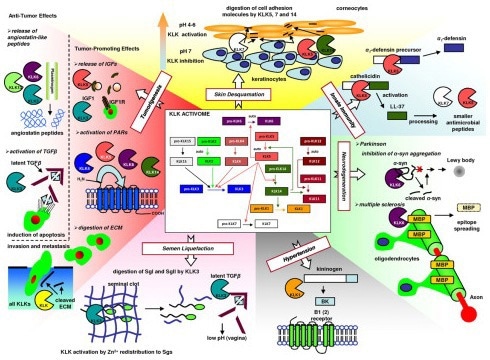

Skin desquamation, semen liquefaction, tooth enamel formation, immune response regulation, and neural development are just a few of the physiological processes in which KLKs are implicated. Conversely, abnormalities in the regulation of KLK are linked to a multitude of pathophysiological processes, including but not limited to cancers of the prostate and ovaries, lung disorders, diabetes, hypertension, and cardiovascular disease.

KLK3 (PSA) for prostate cancer, KLK6 and KLK10 for ovarian cancer, and KLK5 and KLK14 for breast cancer are a few of the most researched KLKs in cancer research. Tumor-promoting or tumor-suppressive factors differentially regulate each KLK's expression in distinct types of cancer. KLKs have an extensive molecular network that interacts with uPAs, PARs, Kinin, TGF-b, and MMPs to promote cancer cells' survival, growth, and metastasis.

KLK regulation mechanisms in normal physiology and disease states. Image Credit: https://doi.org/10.1074/jbc.R109.027946.